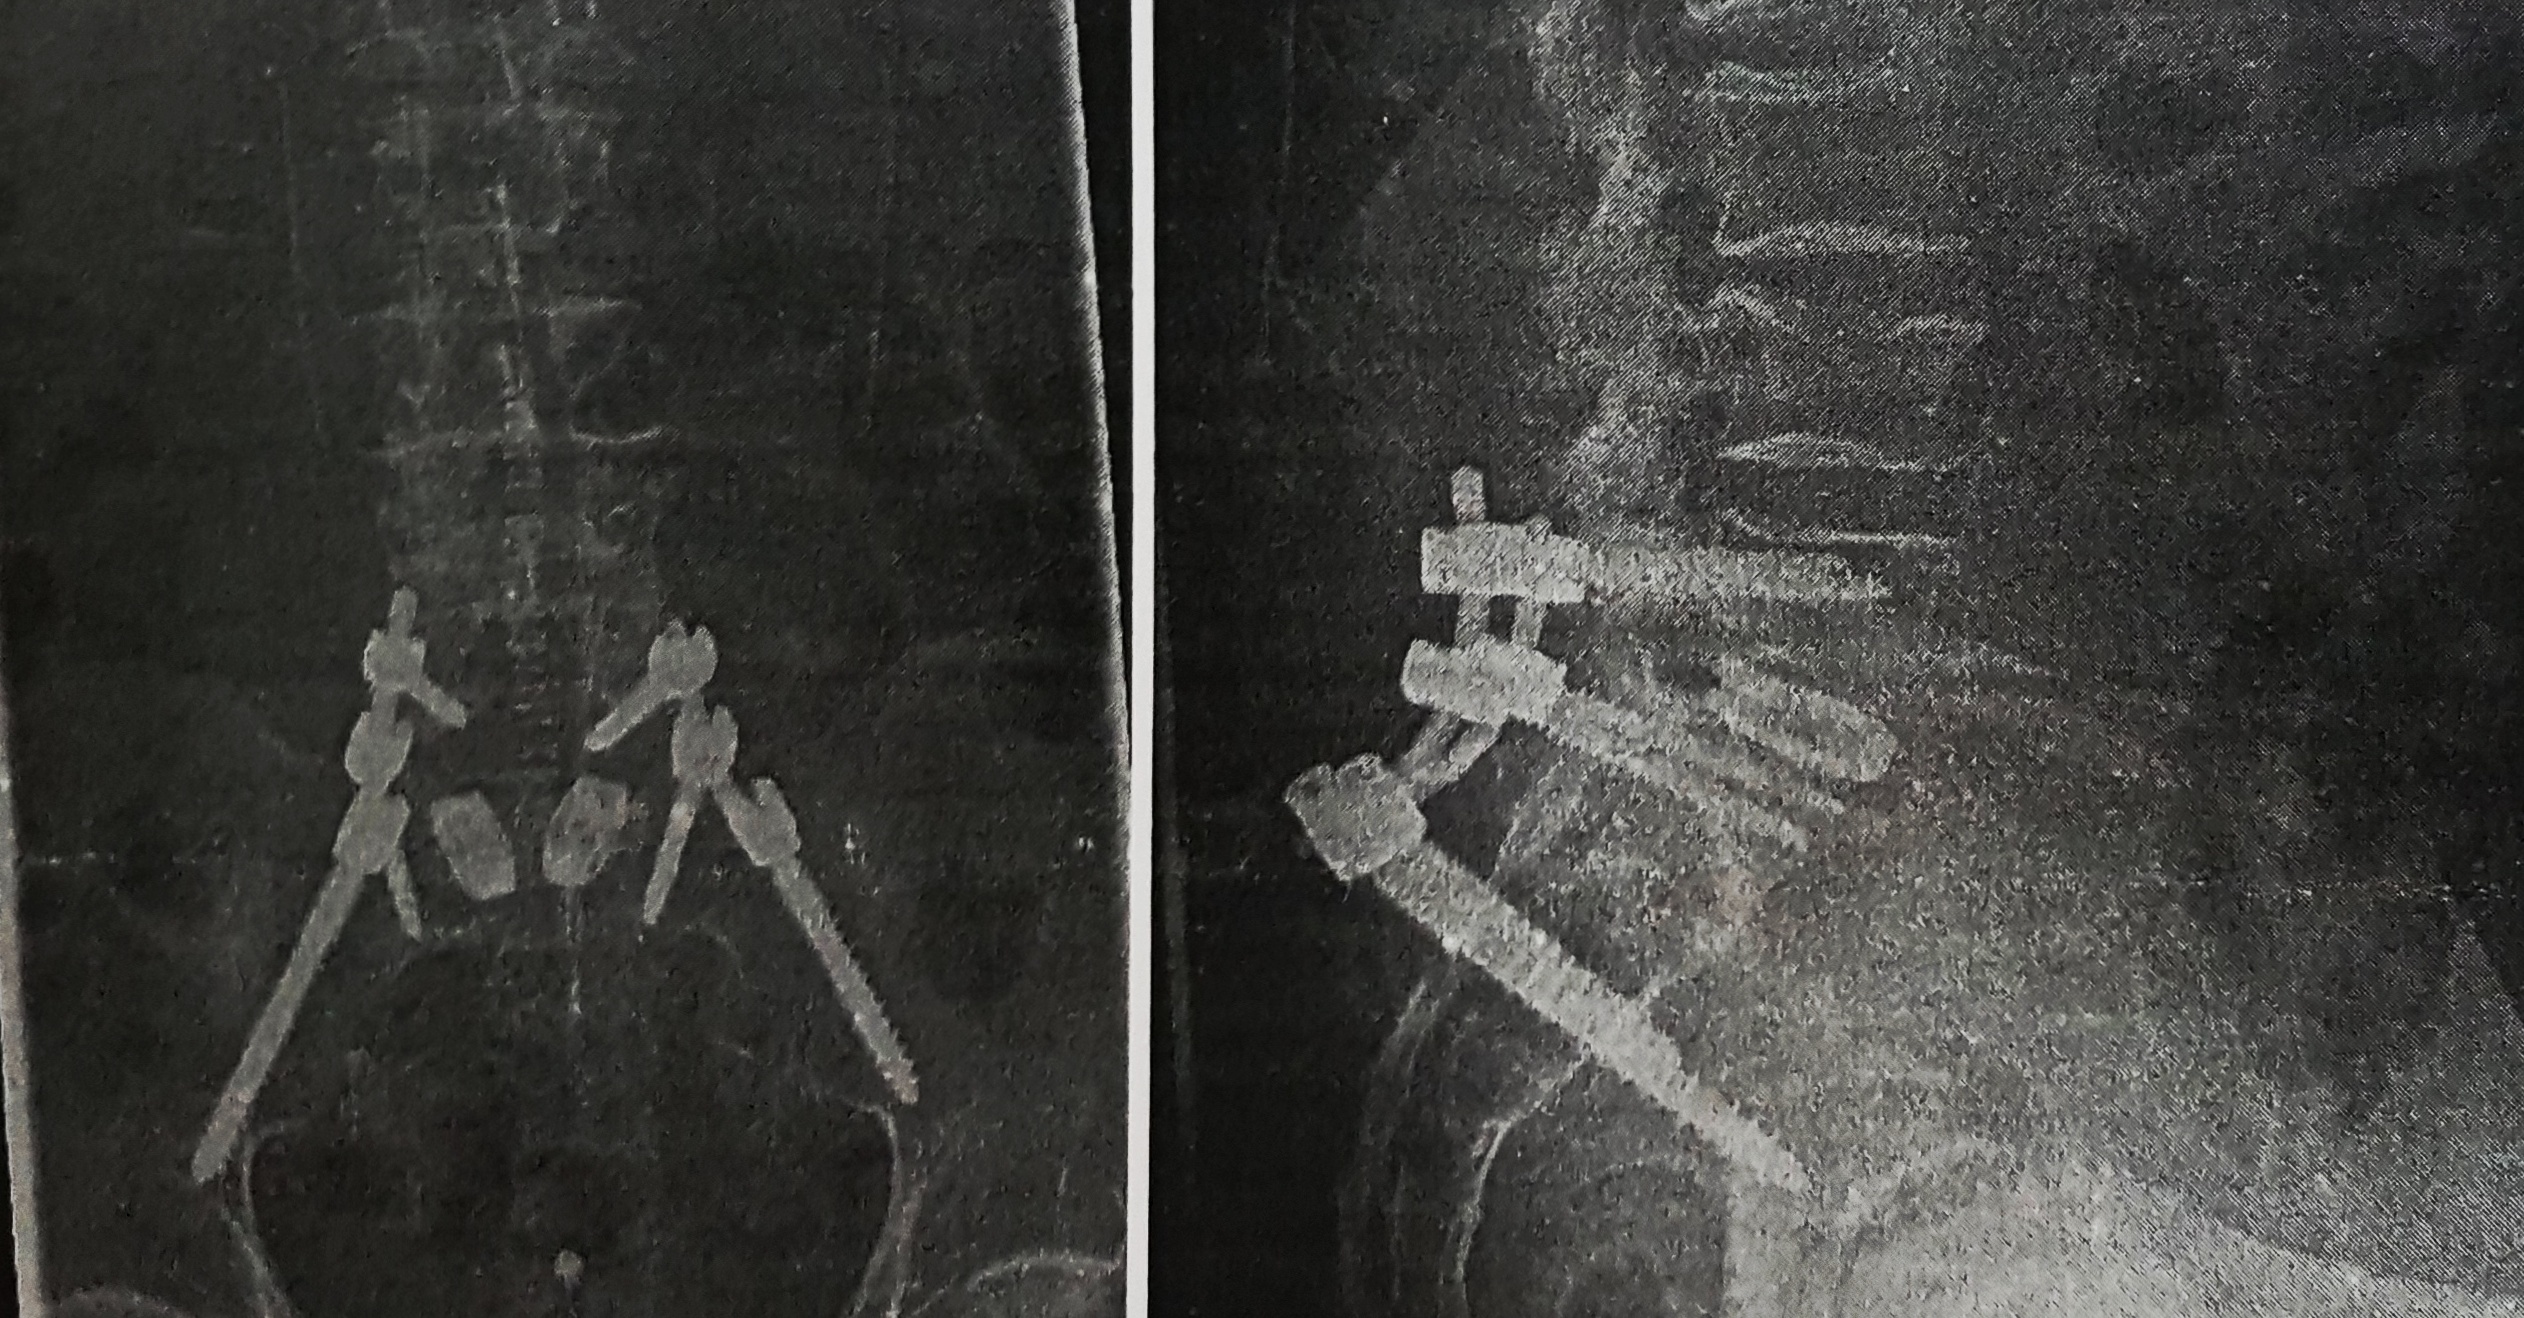

Scheisse, nochmal das Gleiche

unerträgliche Schmerzen.

Dies veranlasst mich trotz grösster Bedenken, nochmal ins Krankenhaus zu gehen

und die ganze OP wiederholen zu lassen.

Ich muss also ohne persönlichen Trost meiner Mary auskommen.

angeblich ist eine Schraube locker ( hab ich mir fast gedacht )

Ein Riss im Becken wurde auch noch festgestellt, also die lockere Schraube durch eine dickere ersetzen und den Riss durch eine Verlängerung der Versteifung überbrücken, d.h. noch zwei zusätzliche Schrauben

aber d